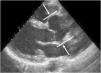

A principal manifestação cardiovascular da SM consiste na dilatação da raiz da aorta e da aorta ascendente proximal com apagamento da junção sino‐tubular, presente em 80% dos doentes, e conduzindo eventualmente à disseção da aorta, principal causa de morte prematura nestes doentes (Figuras 5 e 6) 3,12,41,49–51. A aorta ascendente é, neste contexto, a porção da árvore arterial mais afetada pelo desenvolvimento aneurismático devido ao seu maior conteúdo em fibras elásticas e à exposição ao stress hemodinâmico repetitivo da ejeção do ventrículo esquerdo2,50,52,53.

O estudo cardiovascular é efetuado habitualmente recorrendo a um ecocardiograma transtorácico, validando‐se o maior valor do diâmetro da raiz da aorta registado ao nível do seio de Valsalva, de entre pelo menos três imagens transtorácicas. O valor medido da raiz da aorta deve ser corrigido de acordo com a idade e a área de superfície corporal e interpretado de acordo com o Z‐score. Roman et al. criaram um nomograma para definição do diâmetro da raiz da aorta em relação com a área de superfície corporal e a idade6,70,71. Se o ecocardiograma transtorácico não permitir uma visualização precisa da aorta proximal, deve realizar‐se ecocardiograma transesofágico, tomografia computadorizada ou ressonância magnética, que também são indicados para o estudo da aorta distal. O uso do mesmo nomograma está indicado para se determinar o valor correto do diâmetro da raiz da aorta6. A ecocardiografia é também importante para a avaliação das alterações morfológicas e funcionais das válvulas mitral e tricúspide.